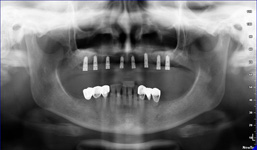

Lékař si vytvoří všechny typy zobrazení potřebných pro naplánování – tedy 2D snímky (panoramatický), příčné řezy i 3D model.

Vidí zde i důležité anatomické útvary – čelistní dutinu, průběh nervu atd. Po proměření množství kosti – šířky i výšky vybere z databáze vhodný typ implantátu a umístí ho do požadované lokality. Ihned vidí jeho pozici ve všech 3 rovinách a na všech snímcích i 3D modelu. Může upravovat podle potřeby jeho pozici, sklon atd.

8) Kontrolní RTG snímek po operaci